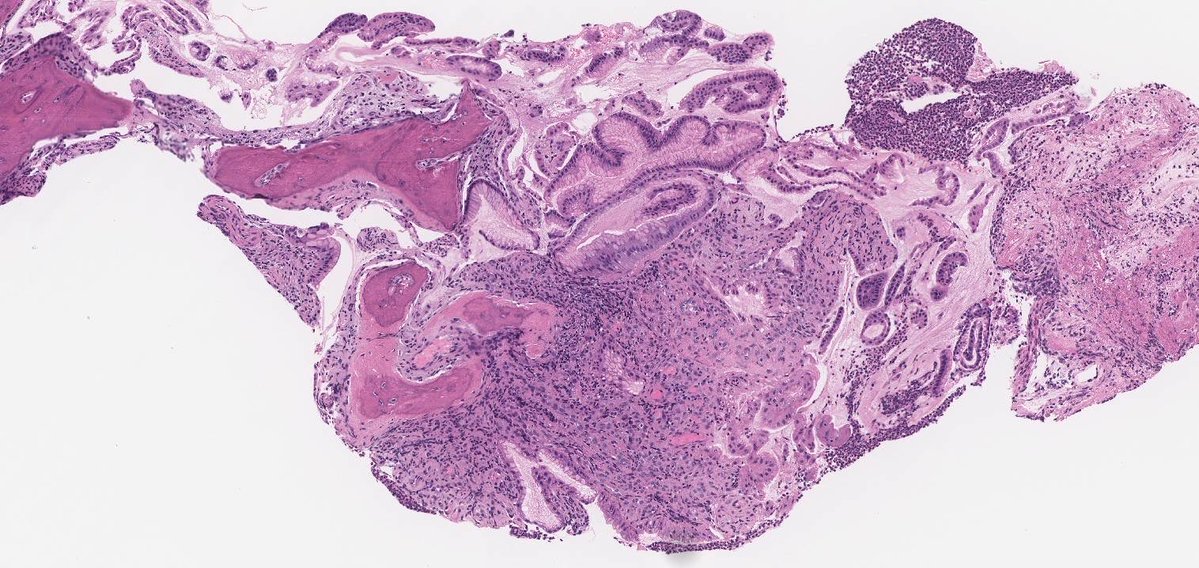

#GUpath #beautyinb9 mimic of prostate cancer on bx: 🔬basal cell hyperplasia